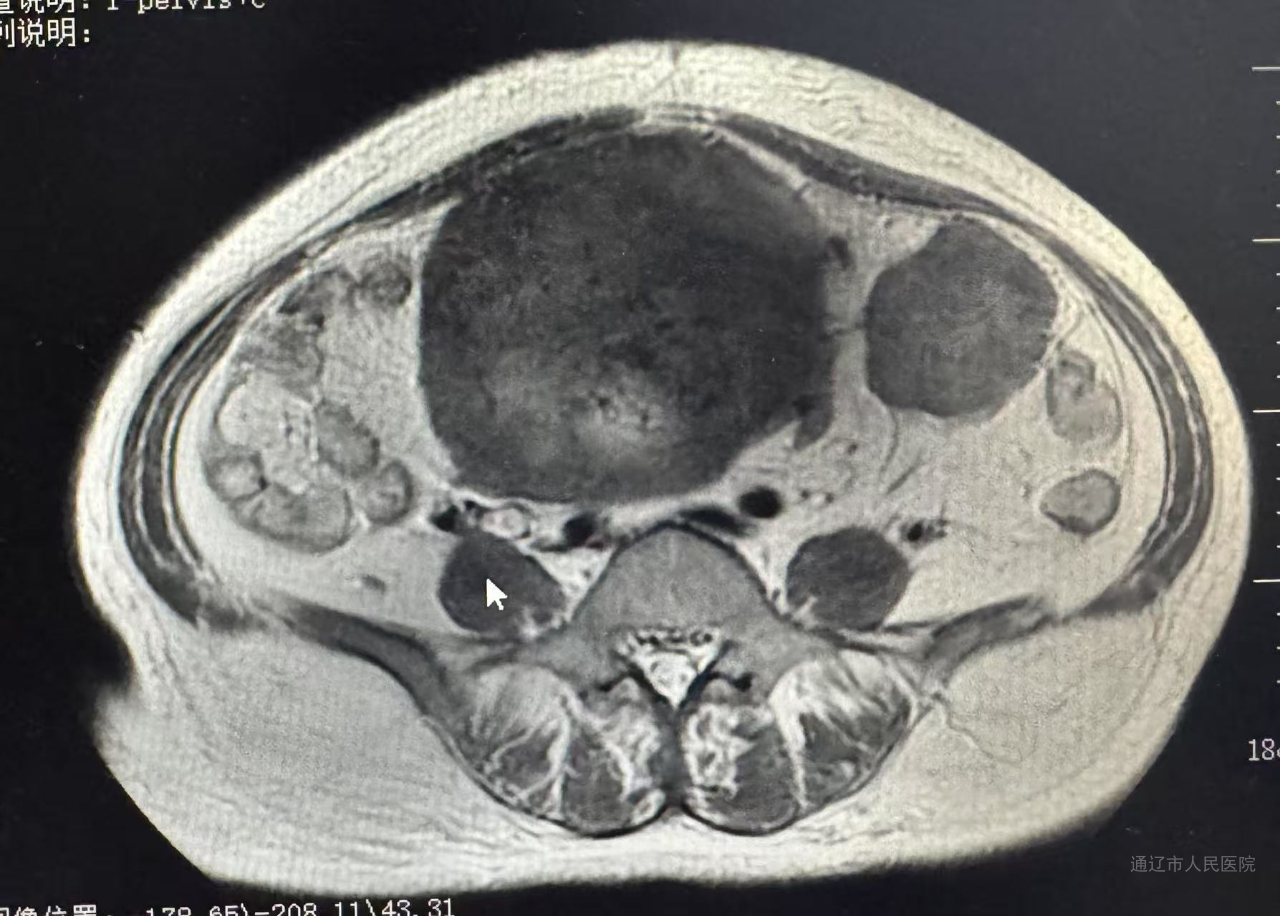

44岁患者左某某痛经10年加重,子宫增大如孕20周(18.3x12.3x17.4cm),经内分泌会诊诊断合并2型糖尿病性酮症、继发贫血及肿瘤标志物CA125>1000。经血管介入科行子宫动脉栓塞止血治疗,后经内分泌科调整血糖后再次转入我科行腹腔镜手术,此次手术依旧由白鹏来主刀,佟金荣、周所霞、程红岩协助,通过旋切器逐步缩小巨大子宫。快速病理结果显示为良性,术后第三天,患者术后第三天恢复良好。